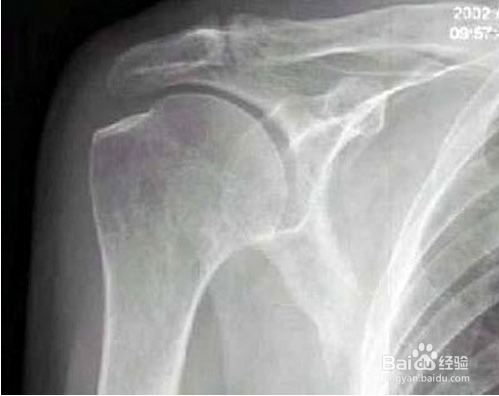

5、 肩关节结核与肩周炎均有肩痛和功能受限,但肩关节结核起病缓慢,常有午后低热、夜晚盗汗、全身乏力、面色苍白、颧部桃红等全身症状。X线片有助诊断,一旦确诊需要针对性的治疗,全身抗结核药物治疗。

6、 肩部周围的肿瘤生长至一定阶段会引起肩痛或伴有肩臂的活动功能障碍。与肩周炎的区别是:患部肩痛逐渐加重,疼痛的部位因肿瘤的生长、局部逐渐肿大而扩大,X线片有助确诊,确诊后积极地治疗。